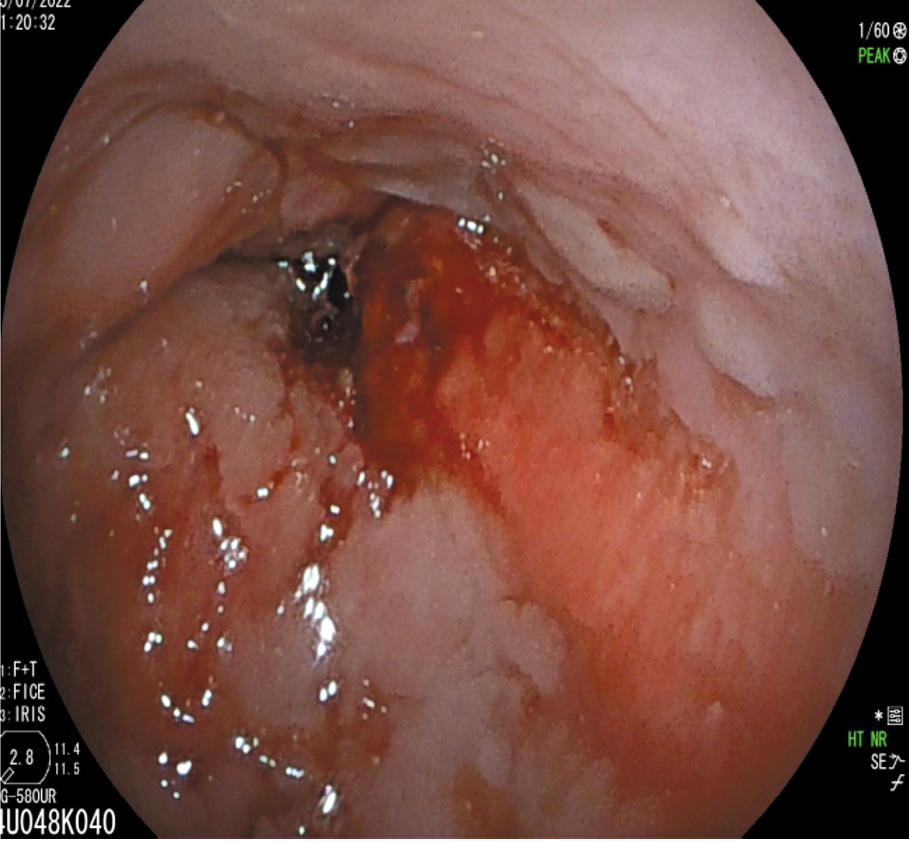

Для иллюстрации последнего приводим рис. 1, 2, где представлена эндоскопическая и эндосонографическая картина стадии Т4а.

Рис. 1. Эндоскопическая картина аденокарциномы нижнегрудного отдела пищевода, развившейся на фоне пищевода Барретта. / Fig. 1. Endoscopic image of the lower thoracic esophagus adenocarcinoma occurred in a patient with Barrett's esophagus.